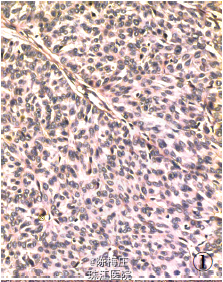

最后诊断:右乳神经内分泌癌;结肠腺癌;左侧卵巢Brenner 瘤。 遂行右乳肿物切除术+ 乙状结肠癌切除术及左侧附件切除术。术中所见:右乳肿物分叶状,与周围界清;乙状结肠肿物与周围无粘连;左侧卵巢肿物包膜完整,未见腹水。术后病理显示右乳腺内分泌癌,乙状结肠腺癌,左侧卵巢Brenner 瘤。